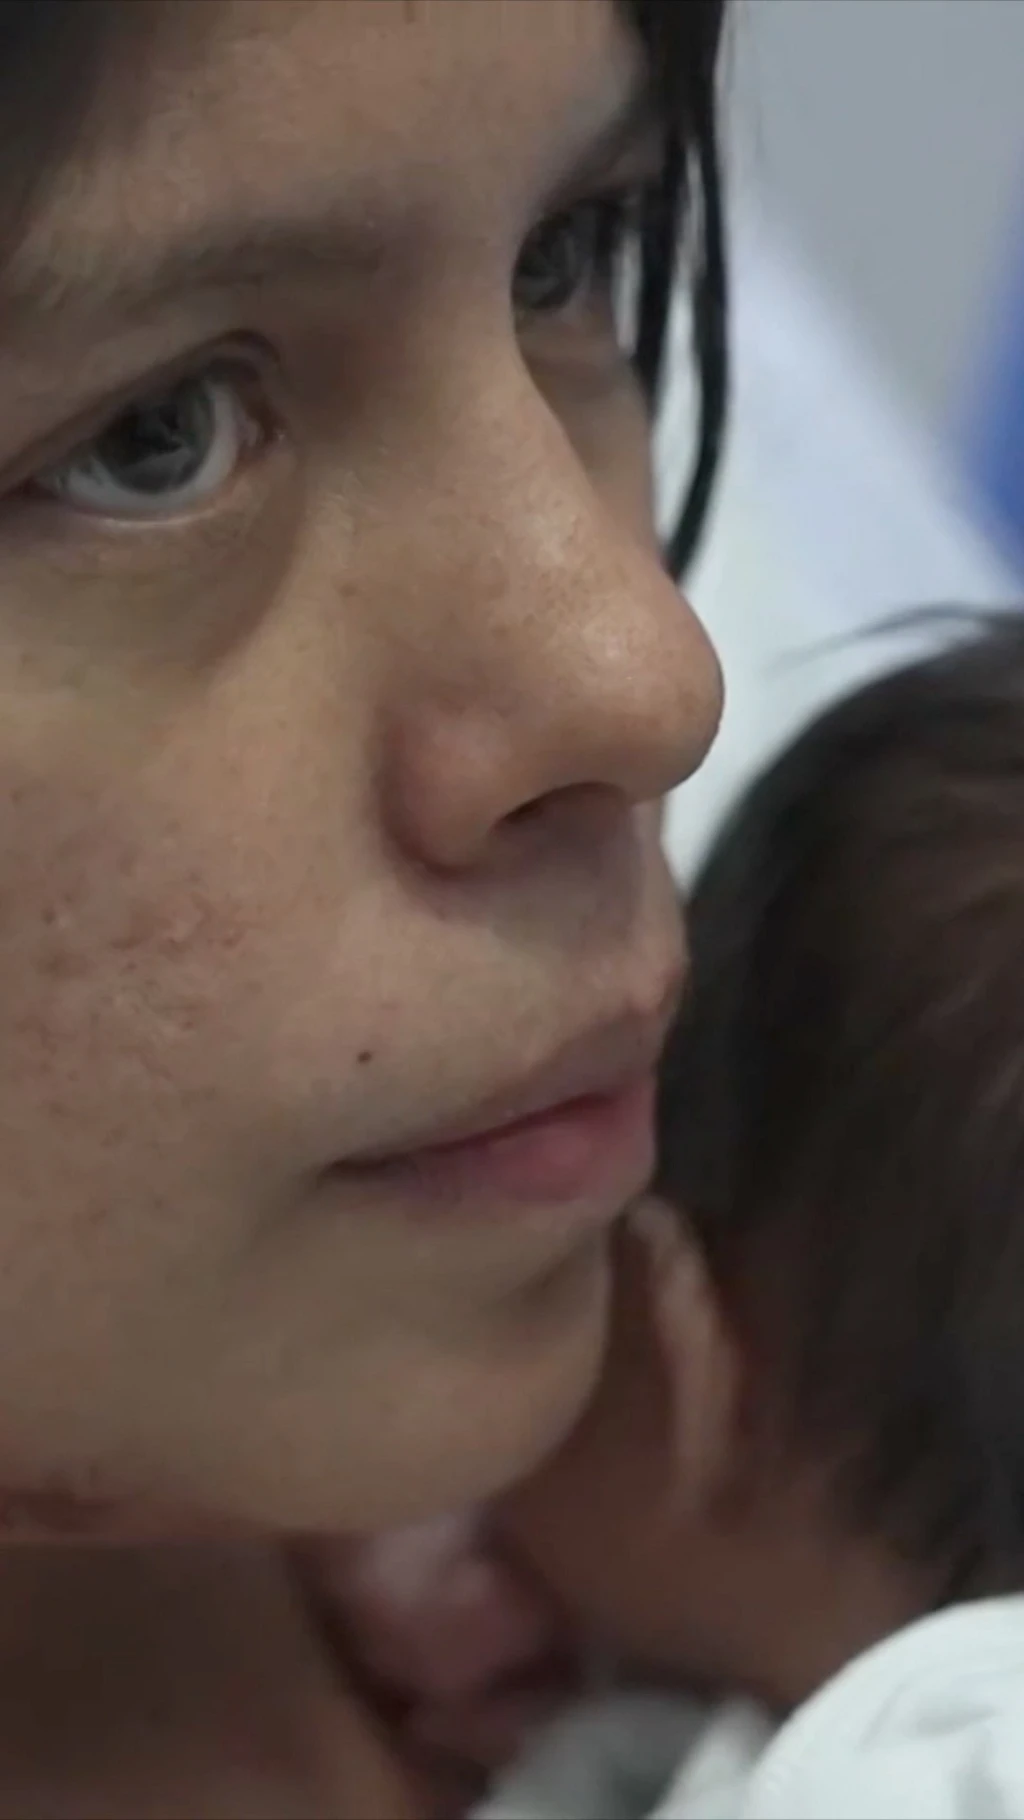

ती ७२ वर्षीय वृद्धले निल्न समस्या भएको गुनासो गरेका थिए। चिकित्सकहरूले उनको नक्कली दाँत फेला पर्नुअघि उनको खकारमा रगत देखिने गरेको थियो।

दुई दिनपछि ती व्यक्ति पुन: समस्या लिएर आएपछि चिकित्सकहरूले उनको घाँटीको जाँच गरेका थिए र त्यहाँ एउटा अर्धगोलाकार आकारको वस्तु अड्किएको फेला पारेका थिए।